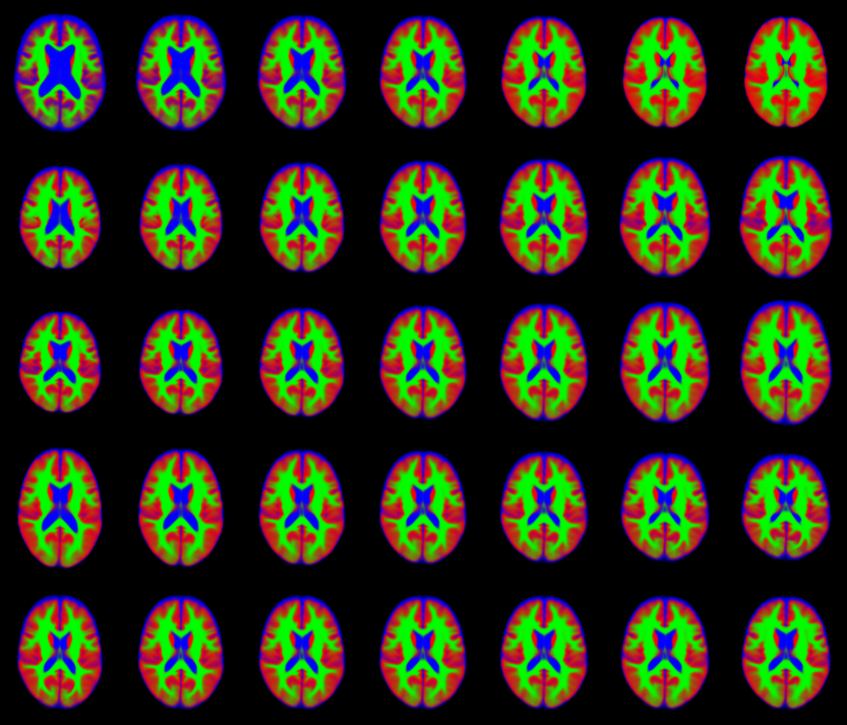

IXI dataset

This example demostrates the multinomial noise model on a single slice through segmented scans from the IXI dataset. The original scans were segmented into grey matter (shown in red), white matter (green) and CSF (blue). The data were fit using 40 components encoding both shape and appearance. These 40 parameters can be used for data mining.

- Original Images (randomly selected from the dataset).

- Full Fit (both shape and appearance).

- Appearance model only.

- Shape model only.

- First 10 modes of variability.